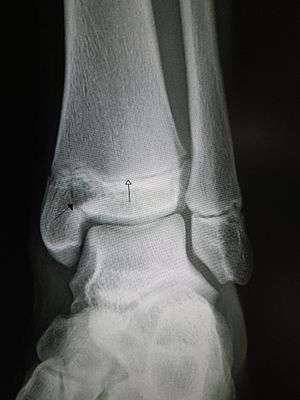

| An X-ray of the left ankle showing a Salter–Harris type III fracture of medial malleolus. Black arrow demonstrates fracture line while the white arrow marks the growth plate. | |

- Type III – A fracture through growth plate and epiphysis, sparing the metaphysis:[5] 8% incidence